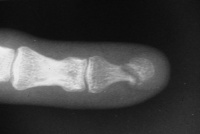

| Case 1. 6 week old grossly unstable distal phalanx fracture. Fracture reduced through a midline palmar approach and stabilized with extraarticular nonparallel Kirschner wires. |